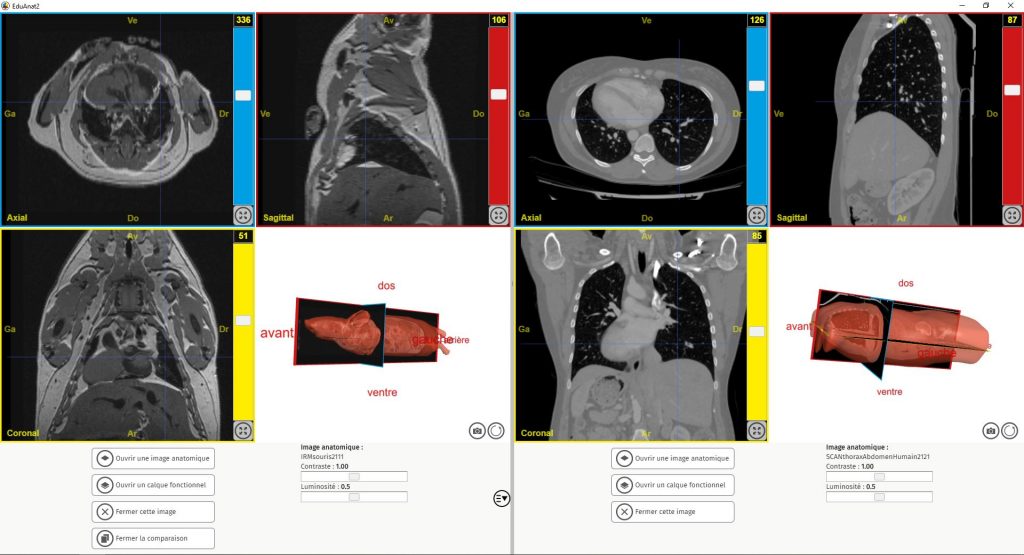

- il est désormais possible de comparer dans une même fenêtre 2 IRM

- pour la quasi totalité des IRM, une reconstitution 3D de la tête ou de l’organe est proposée

La banque d’images qui lui était associée, NeuroPeda, est elle remplacée par une banque élargie, AnaPeda, qui contient (rassurez-vous) l’intégralité des anciennes IRM converties au nouveau format (le format NIFTI, plus moderne). AnaPeda contient également de nouvelles images, notamment en lien avec les nouveaux programmes. Elle contient aussi des IRM et des CT-Scans sans rapport avec les neurosciences, comme par exemple des IRM de souris et de grenouille (pour étudier les plans d’organisation), un scan thorax+abdomen humain et même une pelote de réjection.